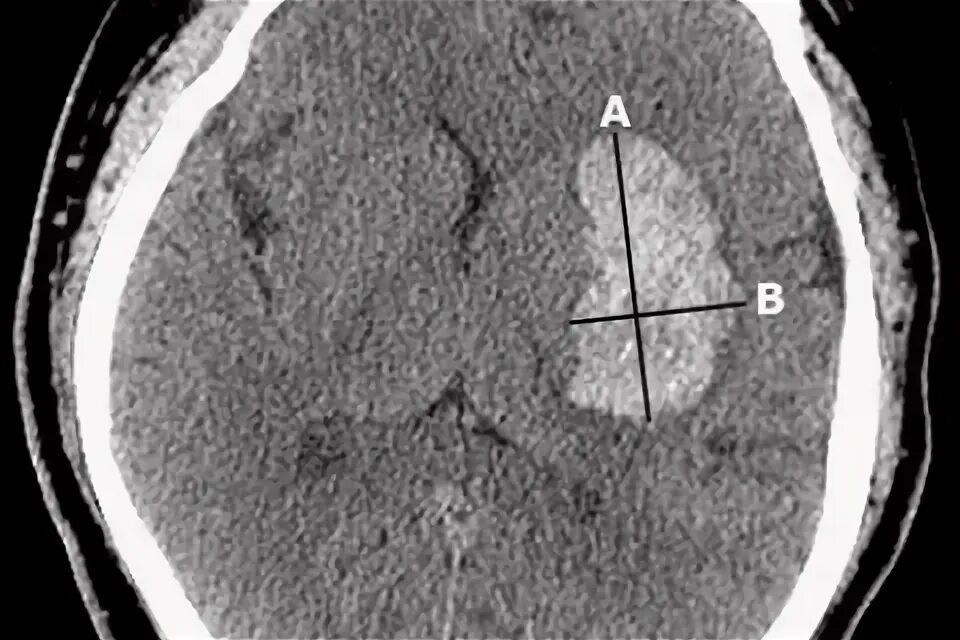

Объем гематомы на кт